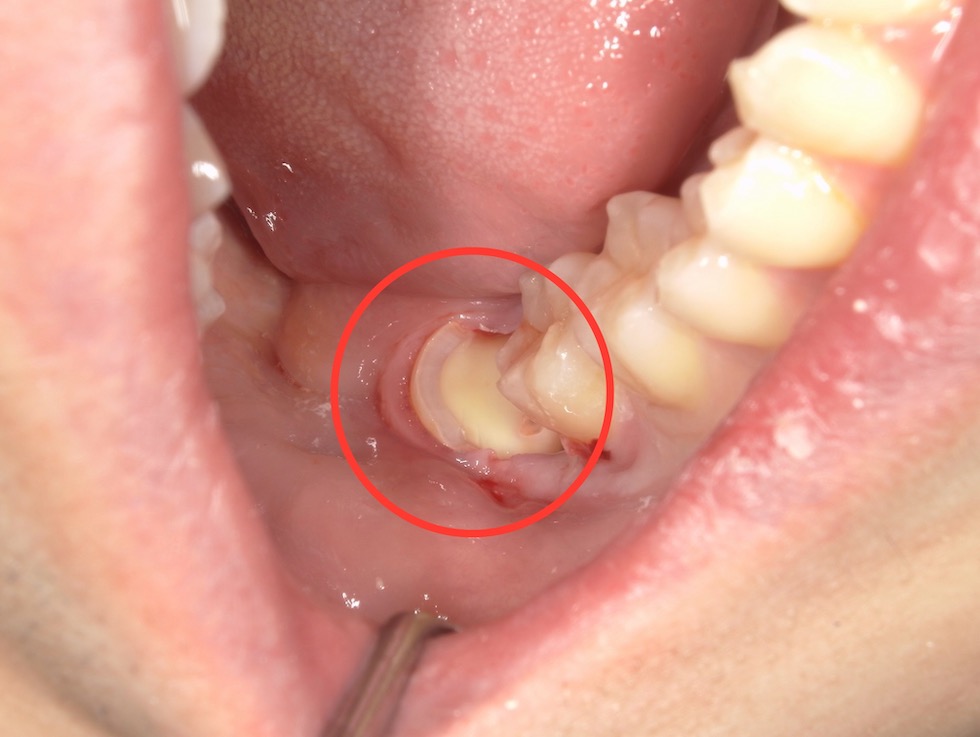

右下の奥歯(親知らず)に食べカスが詰まり歯茎が腫れていました。数年前より繰り返しており、診査の結果、「智歯周囲炎」と診断しました。原因は親知らずであると診断したため抜歯を行うこととなりました。

レントゲンで確認したところ、右下の親知らずは斜めに生えていました。手前には健康な歯があり傷をつけられないため、抜歯する親知らずを分割して抜歯をすることになりました。部分麻酔を行ったのち、初めに歯冠(歯の頭の部分)を2つに割って取り、その後、歯根(歯の根の部分)を引き上げることで抜歯を行いました。傷口がやや広いため、1カ所だけ縫合しました。抜歯後の注意事項をご説明し、抗生物質と鎮痛剤を処方しました。